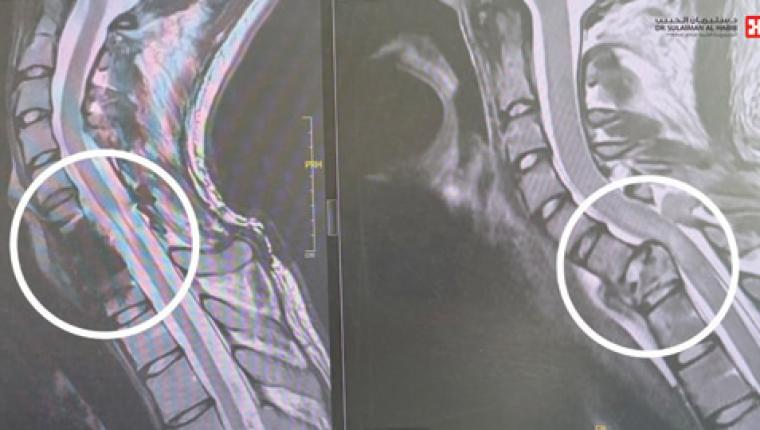

مستشفى الدكتور سليمان الحبيب بالقصيم ينقذ شاباً من الشلل المحتم